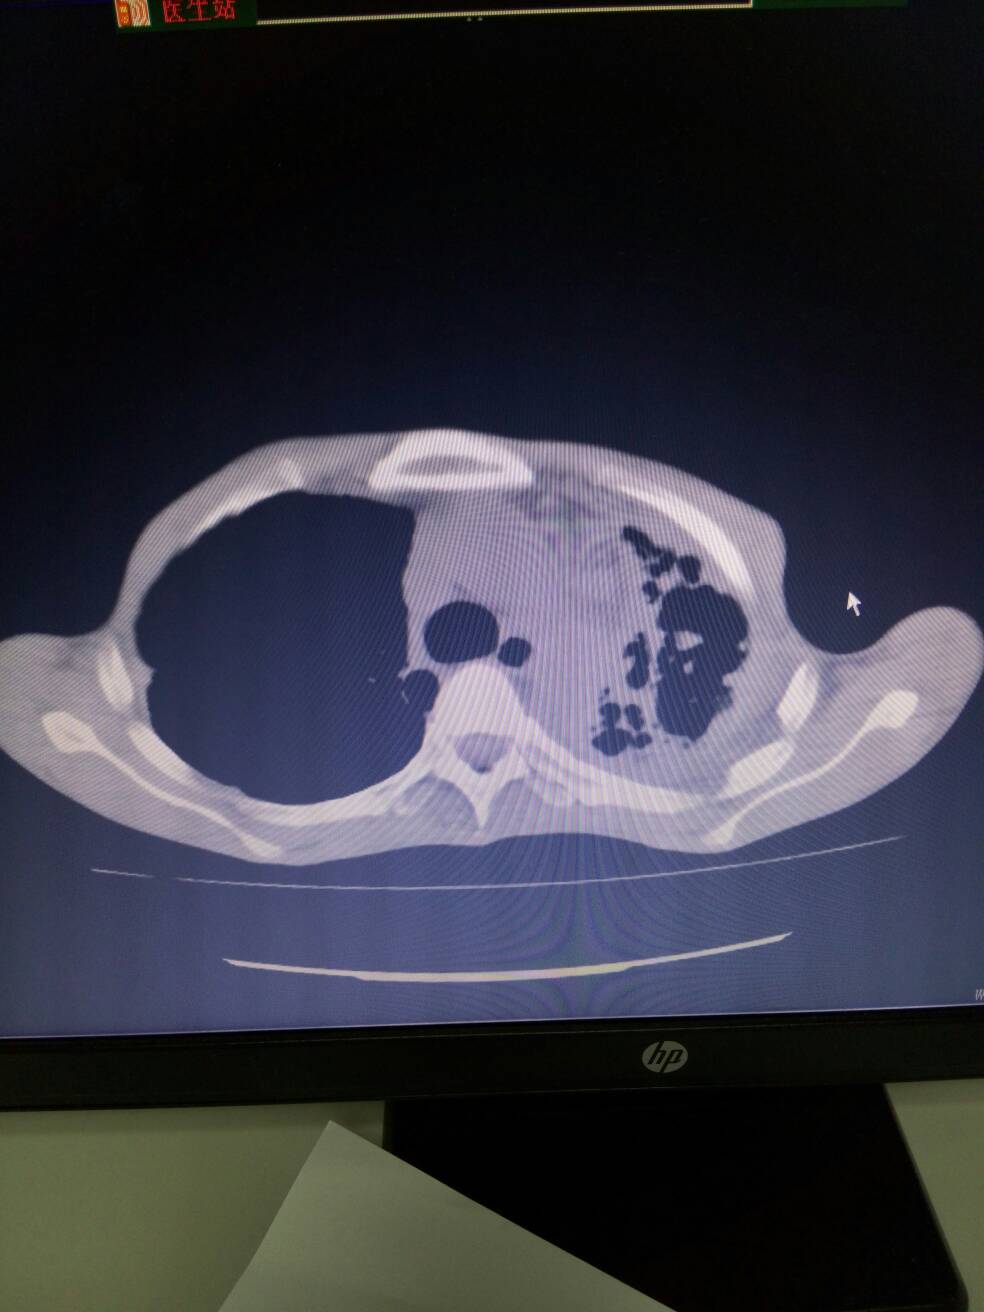

1.左上肺体积缩小,呈多囊状改变,不除外左肺发育不良并感染可能。2.双肺散在感染。3.右上肺多发肺大疱。4.两侧胸膜增厚,左侧伴钙化。5.纵膈多发增大淋巴结。